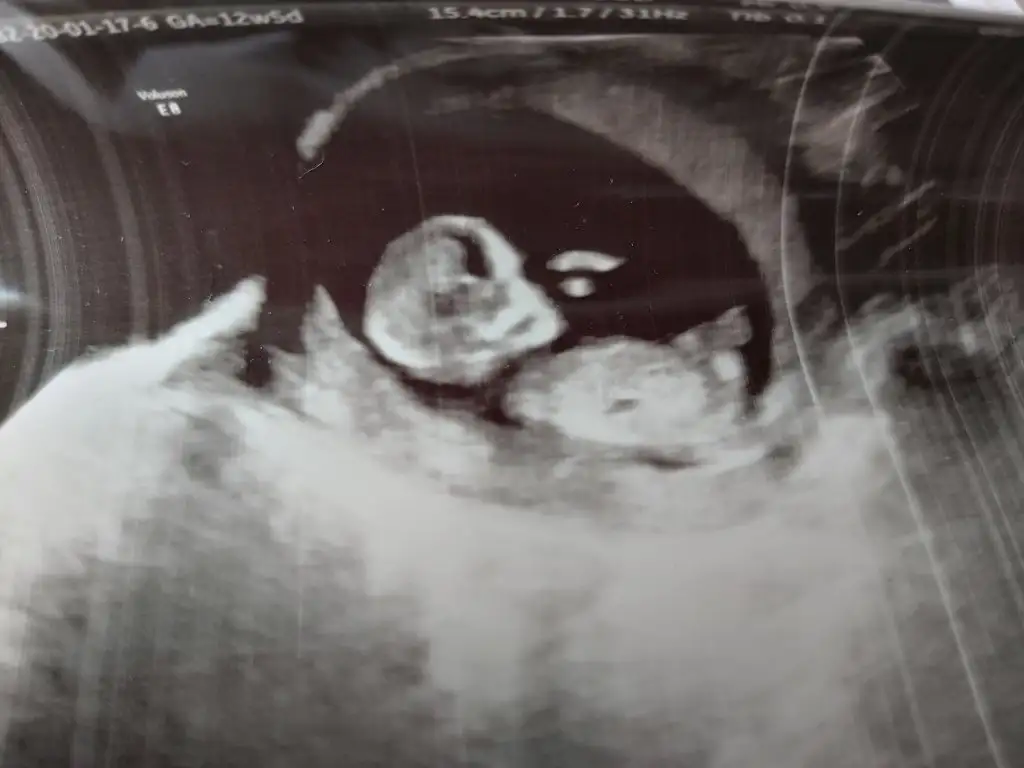

dr soylemeden siz gorun genital nub teorisi ( bebegin cinsiyeti)

Net degil usg 11+ yada 12+ oldugunda paylaşın yada net varsa usg paylaşın

mrhaba lütfen yorumlarmisiniz sizce kızmı erkekmi bi arkadas icin soruyorum